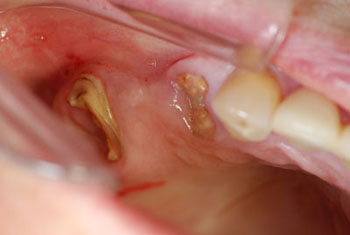

- Wurzelreste

- Extraktion

- leere Alveolen

Mit den minimalinvasiven Sofortimplantaten als Zahnimplantate nach Extraktion gibt es ein Verfahren, das Zahnverlust nach Zahnextraktion sofort ersetzt und in nur einer Sitzung durch ein Zahnimplantat wieder zu einer neuen festen Zahnwurzel verhilft. Sofort nach Zahnextraktion des nicht erhaltungswürdigen stark zerstörten Zahnes wird das "Zahnloch" gesäubert. Im gleichen Moment setzt schon die Heilung ein. In der Zeit vor der Zahnimplantation, musste sich der Körper viel mit der entzündeten Region beschäftigen. Die Immunabwehr schickte Antikörper und Aufräumarbeiten und Knochenaufbauzellen um mit der bakteriellen Bedrohung aus dem faulen Zahn fertig zu werden. Jede Entzündung fördert eine bis zu 5 Fach höhere Durchblutung im Vergleich zum Normalzustand. Dazu bildet der Körper viele neue Blutgefäße, um die Körperabwehrzellen zu dem kranken infektiösen Zahn zu bringen. Der Organismus baut sozusagen eine Autobahn ins Krisengebiet. Sofort nach Zahnextraktion und Wundreinigung werden diese Autobahnen genutzt, um über erhöhte Durchblutung Knochenaufbauzellen zu schicken. Der weitere Heilungsprozess läuft daher um ein Vielfaches schneller und einfacher ab. Auch die Körperabwehr ist noch in hoher Stärke vor Ort und die Zahnimplantation kommt mit nur wenig oder keiner Antibiotikagabe aus.

Die Patientin war begeistert während und nach der Behandlung kaum Schmerz verspürt zu haben. Die Patientin hat sich lieber für neue funktionsfähige Zirkonkronen auf Zahnimplantaten, statt einer herausnehmbaren Prothese entschieden. Der stark zerstörte Zahn wurde entfernt und durch ein Zahnimplantat als Sofortimplantat ersetzt. Nach Entfernen der Ursache von Zahnschmerz Bakterien und Eiter heilte die Patientin unter kurzer Einnahme von Antibiotikum sehr schnell und komplikationslos. In 6-8 Wochen (12 Wochen bei Rauchern) bekommt Sie Ihre metallfreien Kronen aus Zirkon. Die Belastung war nicht viel größer als bei einer Zahnextraktion alleine. Die minimalinvasive Sofortimplantation verspricht ein schöneres Zahnfleischergebnis, der Zahn liegt nicht auf dem Zahnfleisch auf, sondern kommt aus dem Zahnfleisch heraus gleich einem Naturzahn. Die Einheilquote ist ebenfalls besser. Der Preis ist gleich, doch benötigt man zusätzlich ein herausnehmbares Provisorium oder erträgt für 6 Wochen die Lücke.